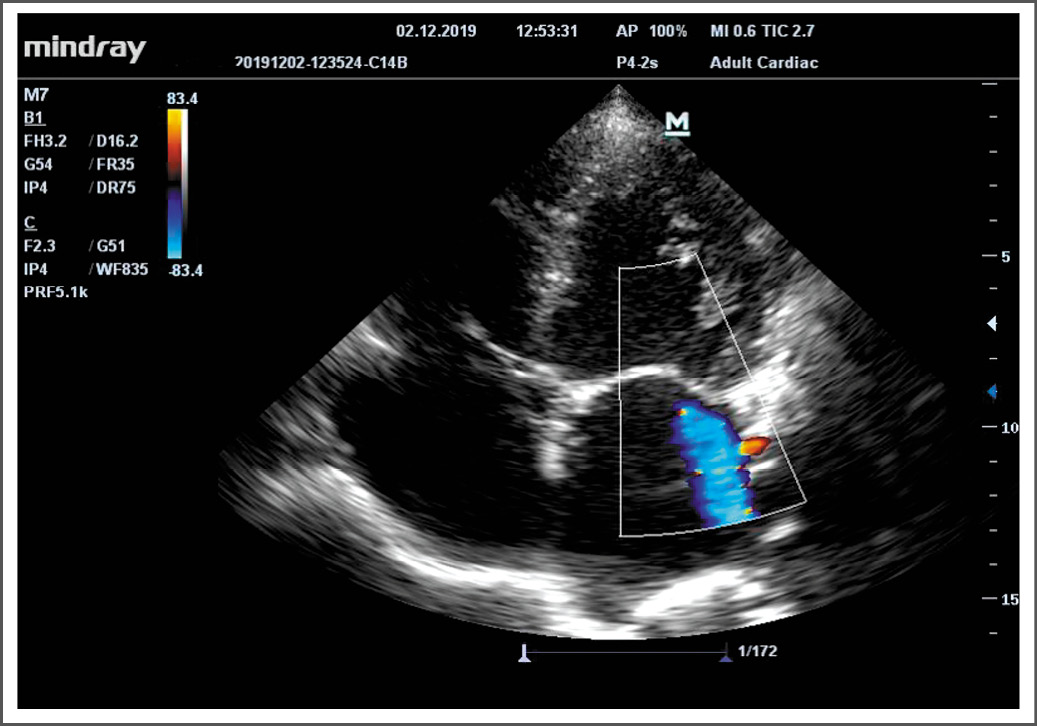

Рис. 2. Эхокардиографическое исследование пациентки Д.Н. Верхушечное 4-х камерное сечение (тяжёлая митральная недостаточность).

Примечание. При доплеровском исследовании митрального клапана определяется струя тяжёлой митральной регургитации.

Fig. 2. Echocardiography of patient D.N. Apical 4-chamber section (severe mitral regurgitation).

Note. Doppler examination of the mitral valve determines the jet of severe mitral regurgitation.